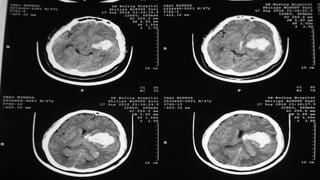

伤后 5h , GCS 13 伤后 6 天 ,GCS 12 分 伤后第 7 天, GCS 4-5 分 Case

伤后 14 天, GCS 12 分 伤后 21 天出院 随访 MRI